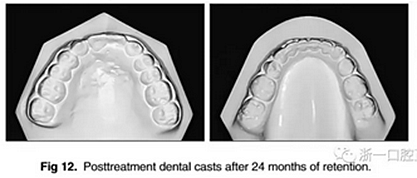

治療持續(xù)3年,患者始終保持積極和合作??谇恍l(wèi)生很好。患者和她的父母都對(duì)結(jié)果感到滿意。經(jīng)過24個(gè)月的保持后,咬合保持得很好(圖11 ; 圖12)。在上牙弓中,應(yīng)用固定舌側(cè)保持器以防止任何復(fù)發(fā)傾向。在下牙弓中,治療后拔除第三磨牙。